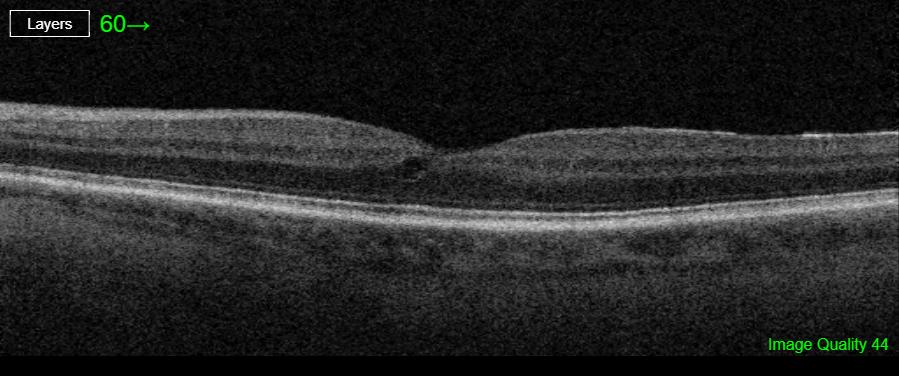

A 79-year-old female came in for a routine follow-up, with no new visual concerns. OCT imaging revealed moderate macular changes in the right eye and mild changes in the left, both causing distortion. Despite this, her vision remains excellent (20/20 OD, 20/25 OS).

This patient has an epiretinal membrane with a lamellar hole in the right eye and mild ERM in the left. OCT imaging shows traction and schisis in the right eye, with a cyst in the left. Visual acuity remains excellent.

A lamellar macular hole is a partial-thickness retinal defect affecting the macula, often associated with traction from an epiretinal membrane (ERM). It typically causes central visual distortion but preserves the outer retinal layers. The condition may lead to subtle visual symptoms, with varying degrees of impact on vision. Management options are generally conservative, focusing on observation unless the hole progresses or vision is significantly impaired.